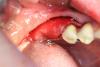

ВИТА Опубликовано 17 августа, 2012 Автор Поделиться Опубликовано 17 августа, 2012 ну вот как то так я делаю...........с помощью спец набора для расщепления........гребень был мм 3, поставила импланты 3,75 в облати 36 и 4,5 в области 37 АВ Ссылка на комментарий

Bier Опубликовано 17 августа, 2012 Поделиться Опубликовано 17 августа, 2012 Вита, в канал не влезли? близко как-то ) мембрану не фиксировали как и я ? Ссылка на комментарий

kmatv Опубликовано 17 августа, 2012 Поделиться Опубликовано 17 августа, 2012 Все вроде и ни чего для начального опыта сплита. Только расщепления-то не было. Судя по фото, вестибулярная стенка даже не сдвинулась, и вы выпилили весь кортикальный слой. Т.е.можно было и не делать распилы. Надо делать послабляющий распил внизу. Ссылка на комментарий

kmatv Опубликовано 17 августа, 2012 Поделиться Опубликовано 17 августа, 2012 Вита, вы не обижайтесь, но тогда смысл этих пропилов? Если кортикалка даже не сдвинулась?! Сплит направлен на раздвижение и сохраниение кортикальной пластинки. Если чувствуете излишнюю подвижность, и высокую вероятность отлома, подфиксируйте минивинтами, и продолжайте закручивать импланты.. Ссылка на комментарий

Mane Опубликовано 21 августа, 2012 Поделиться Опубликовано 21 августа, 2012 Тоже поддержку что расщепления здесь и не было. Ситуация еще хуже чем в теме "расщепление по карлосу" которое представил биер. Не хватает горизонтального пропила внизу что как раз и дало бы почву для сплита. Опять же вы просто вписали эти имплантаты в то что было и сверху просыпались. Блоков не нужно бояться. Если их делать много и часто то результат вас будет так радовать, что расщепление вам делать уже не захочется. Без обид. 1 Ссылка на комментарий

Bier Опубликовано 22 августа, 2012 Поделиться Опубликовано 22 августа, 2012 Сева и kmatv,расщепление там все же происходит, лепестки несколько расходятся. Посмотрите те же работы Карлоса. У нас есть в этом отношении принципиальные отличия или почему вы тогда там промолчали? Я так понимаю, что смысл метода в том, чтобы вписать имплантат в нативную кость, а затем для предотвращения резорбции хорошенечко ее присыпать. Ссылка на комментарий